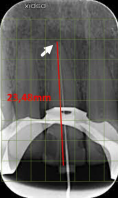

- Mesure : très utile en endodontie pour mesurer la longueur de travail.